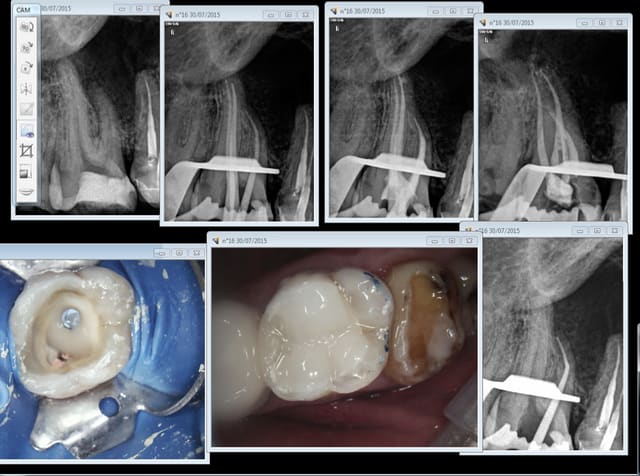

1 .Essayage cones en place, couper ce qui dépasse le cas échéant ( une sur instrumentation ca arrive)

2. scellement des cones.

3. couper les cones au friendo puis phase de descente au friendo ( qui est un heater plugger je le rappelle) et compactage au machtou.

4. coincer les chutes de gutta à l' entrée des canaux et les thermo-compacter au mac spadden.

30/07/2015 à 14h53

Ca c'est pas mal non plus en 45 mn, on se demande pourquoi thermo compacer au mac spadden et j'ai perdu un morceau de crochet au passage ! -)))))

Endo 16 + sc 33. Costeaude la racine DV.

Capture d e cran 2015 07 30 15.33 - Eugenol